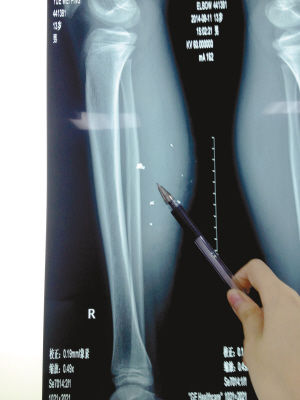

X光片顯示:手機(jī)電池內(nèi)的物質(zhì)被炸進(jìn)了小平的右小腿里

8月10日凌晨,小平轉(zhuǎn)院至重慶醫(yī)科大學(xué)附屬兒童醫(yī)院。小平的主治醫(yī)生骨科二病房周悅航醫(yī)生介紹,入院時小平右小腿腫脹,經(jīng)檢查,發(fā)現(xiàn)有爆炸傷伴異物殘留。傷口較深,約1.5厘米~2厘米,手機(jī)爆炸后進(jìn)入患兒小腿的異物約有10處。周悅航說,由于進(jìn)入皮膚的異物較多,已深入肌肉,且比較分散,最深的一塊貼近骨頭,可能需要多次手術(shù)。

另外,醫(yī)生擔(dān)心手機(jī)爆炸后金屬物進(jìn)入患兒體內(nèi)可能會對患兒肌肉造成損傷,所以需盡快手術(shù)。據(jù)悉,8月14日上午,小平將接受小腿爆炸傷清創(chuàng)與異物取出術(shù)。